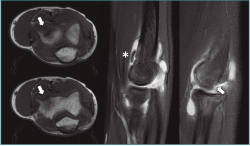

La tomografía computarizada (TC) permite una mejor definición del defecto. La resonancia magnética (RM) muestra edema óseo en las fases más iniciales(1). Además, esta última permite medir el tamaño y la extensión del defecto articular, que es esencial para planificar el tratamiento. En fases iniciales, se aprecian cambios en las secuencias T1 con aspecto normal en T2 (Figura 2). Cuando comienza a fragmentarse, se origina una señal hiperintensa alrededor de la lesión detectable en la secuencia T2, signo demostrativo de inestabilidad. Jans et al.(8) determinaron que la RM tiene una sensibilidad del 100% para diagnosticar una lesión inestable. Además, es extremadamente efectiva para localizar cuerpos libres, que aparecen en el 36% de los casos y que se calcifican con el tiempo, localizándose en la cámara anterior o la gotiera lateral (Figura 3).

Figura 3. Imágenes de resonancia magnética de una osteocondritis disecante de codo de tipo IV de la International Cartilage Repair Society (ICRS). Se aprecia el defecto en los planos transversal y sagital en la región anteroinferior del capitellum (flechas) y cuerpo libre en la cámara anterior (asterisco).